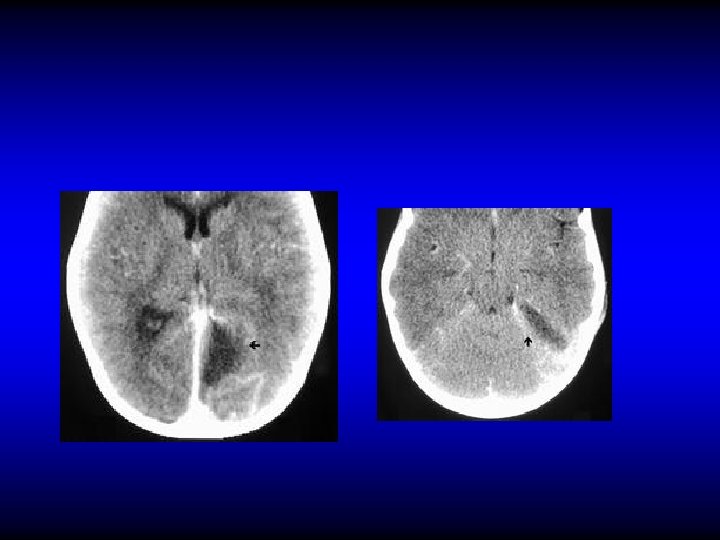

Otogenic brain abscess • 25% of children's and 50% of adult’s brain abscesses are otogenic • Mostly in temporal lobe or cerebellum (2: 1)

Otogenic brain abscess Clinical manifestations • General manifestations: fever, lethargy, headache. • Manifestation of raised IC pressure • Focal manifestations – Temporal: Aphasia, hemianopia, paralysis – Cerebellar: ataxia, vertigo, nystagmus, muscle incoordination

Otogenic brain abscess Diagnosis • CT • MRI

CT